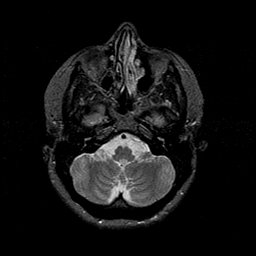

MR Study #1 -- Slice #13